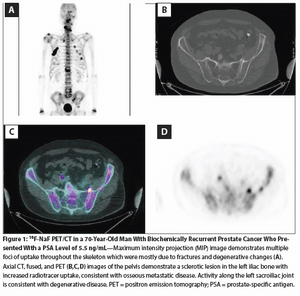

We briefly review these two imaging technologies and provide potential utilization strategies based on available data.